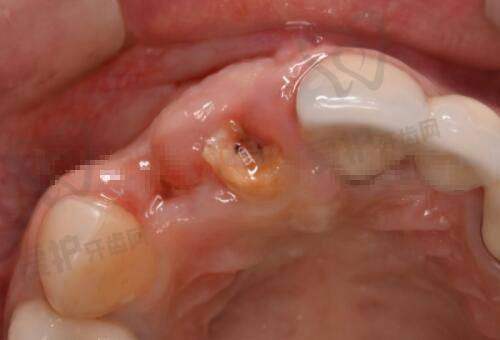

钟春根医生是一位有着20年以上从业经验的口腔美容医生,擅长口腔种植及种植修复、人工智能数字化种植、前牙美学即刻种植、牙槽骨增量技术、上颌窦内外提升术、即刻种植即刻修复,全口无牙颌种植修复等。他凭借不错的技术,为众多患者解决了口腔问题,修复了口腔健康和美观。

高苏健医生同样有着20年以上的从业经验,专注于前牙区的美学种植修复、即刻微创种植、全口无牙颌的种植修复,烤瓷美容牙及微创瓷贴面的精细修复,应用激光技术治疗口腔常见病。他的专精和耐心,让患者在治疗过程中感受到了安心和舒适。

刘佺医生也是口腔美容领域的骨干医生,擅长儿童及成人各类型牙齿畸形矫治、隐形矫治、功能矫治、直丝弓矫治及各类牙齿美容修复、嵌体/贴面修复、微创拔牙、牙髓病及根尖周病的治疗。他对患者认真负责,根据不同患者的情况制定个性化的治疗方案,深受患者好评。